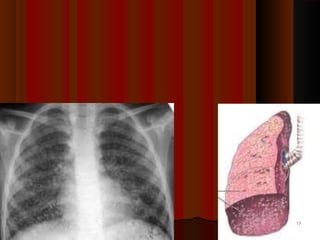

Miliary TuberculosisMiliary Tuberculosis

 This is a severe form of tuberculosis. occurs due to widespreadThis is a severe form of tuberculosis. occurs due to widespread

dissemination tuberculosis through lymphohematogenous route.dissemination tuberculosis through lymphohematogenous route.

 Due to rupture of tuberculous {G}focusDue to rupture of tuberculous {G}focus

 This dissemination can be either confined to lung or may spread toThis dissemination can be either confined to lung or may spread to

other organs too.other organs too.

 There are multiple small millet type wide spread lesions.There are multiple small millet type wide spread lesions.

 Microscopically these lesions show features of granulomatousMicroscopically these lesions show features of granulomatous

inflammation with caseous necrosis.inflammation with caseous necrosis.